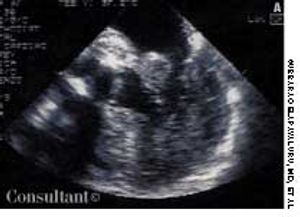

A 75-year-old woman with a bioprosthetic aortic valve, who had undergone surgical repair of an aortic root aneurysm 9 months earlier was hospitalized with fever, headache, and altered mental status of 1-day's duration.